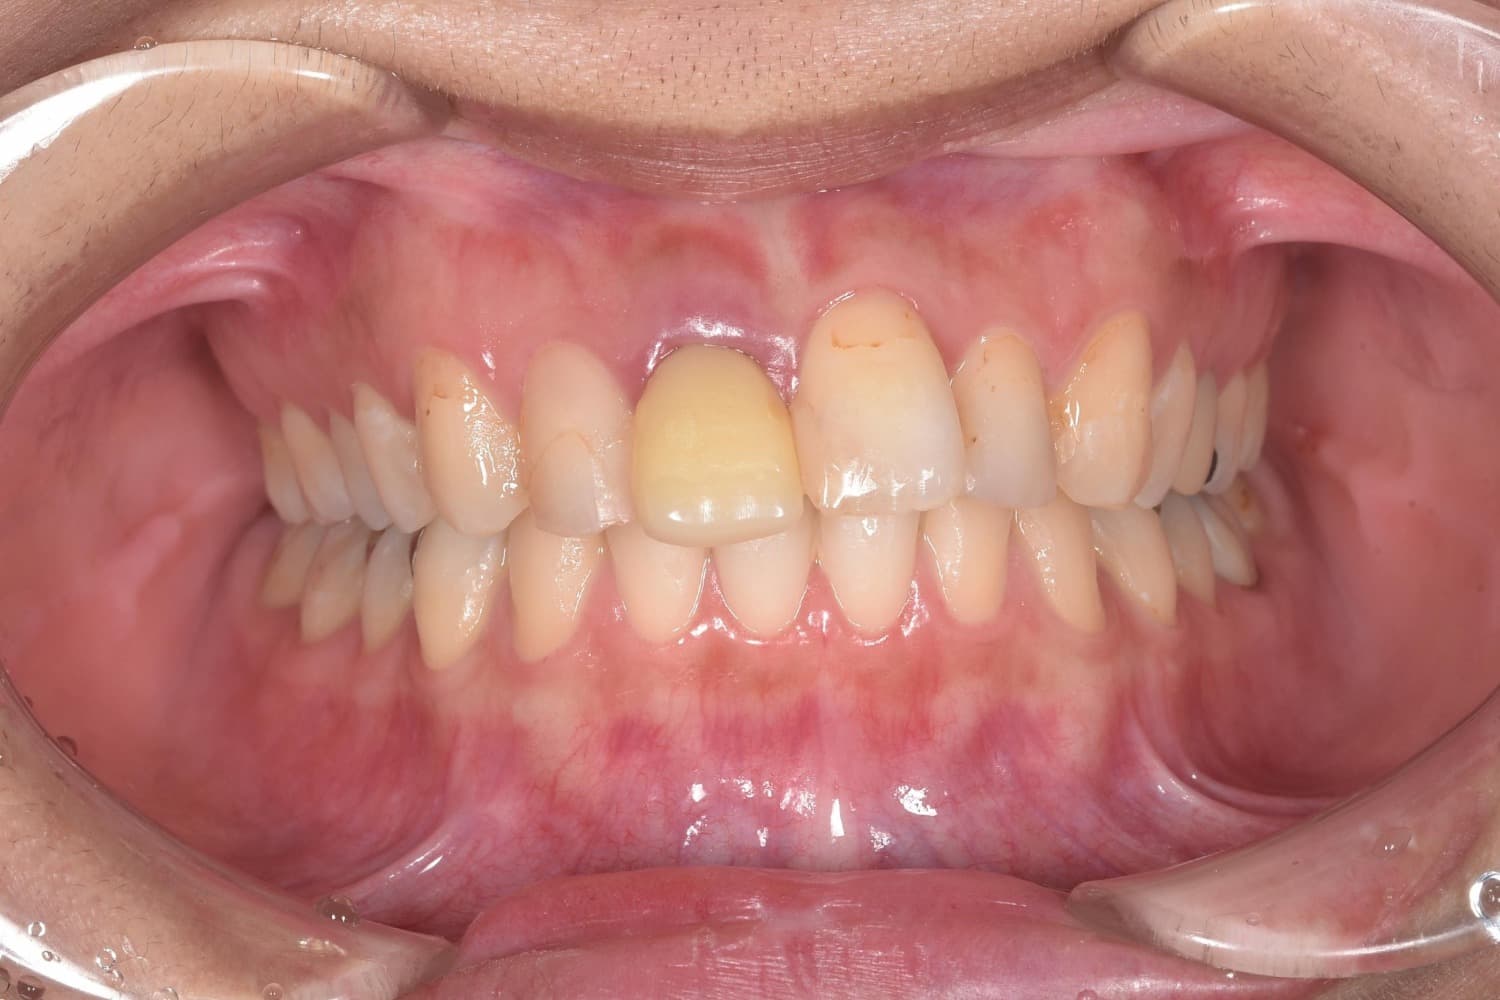

右上1番目のインプラント治療

Before

After

右上1番目の歯を抜歯と同時にインプラントを埋入。 同日に仮歯を装着し、3カ月後にはインプラント上部構造を装着。 インプラント治療により、歯肉のラインを揃え審美的な回復を行いました。

年齢

30代

性別

女性

主訴

右上の前歯が折れた。元々見た目も気になっていた。

治療期間

3ヵ月

治療回数

6回

費用

約47万円

副作用・リスク

インプラントの結合不良、清掃不良による治癒不全